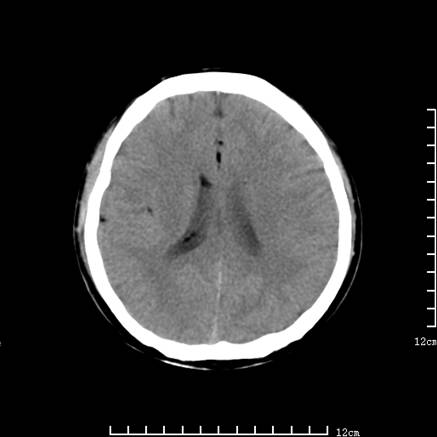

以下是引用jiajie在2008-9-5 22:25:00的发言:[br]男,22岁,头痛1月余。脑室、脑池内病变ct值约-120hu。[br][br]双侧侧脑室内低密度影充填,出现脑脊液脂肪平面,脑池内亦可见弥散分布的斑点状低密度影,脑室脑池未见明显扩大。[br]考虑胆脂瘤破裂后内容物进入脑脊液。